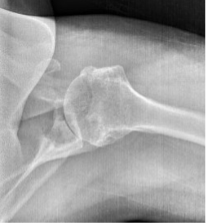

BH is a right hand dominant 70-year-old female, who is retired and moderately active. She presents with 8 months of progressively worsening left shoulder pain affecting her ADLS, sleep and recreational activities. She is 10 years s/p a right anatomic total shoulder arthroplasty. Radiographs and advanced imaging reveal glenohumeral joint advanced degenerative joint disease with an intact rotator cuff. Preoperative planning reveals a native 3 degrees of retroversion with 0 degrees of inclination. As she was extremely happy with the fully functional contralateral shoulder she has enjoyed for the past decade, she was interested in the same solution – an anatomic total shoulder arthroplasty.

At age 70 secondary rotator cuff tears following anatomic total shoulder arthroplasty must be weighed against complications and postoperative function of reverse shoulder arthroplasty [3]. Exactech Predict+ was able to demonstrate comparable postoperative function, scores, pain, and complications. A decision was reached to proceed successfully with an anatomic total shoulder arthroplasty.